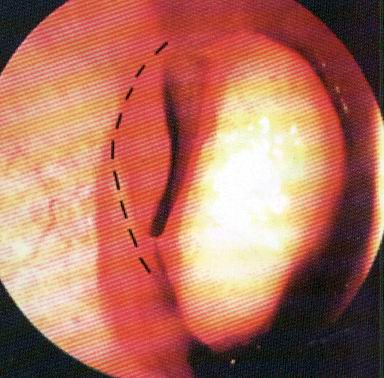

Простой синуслифтинг. Часть III.